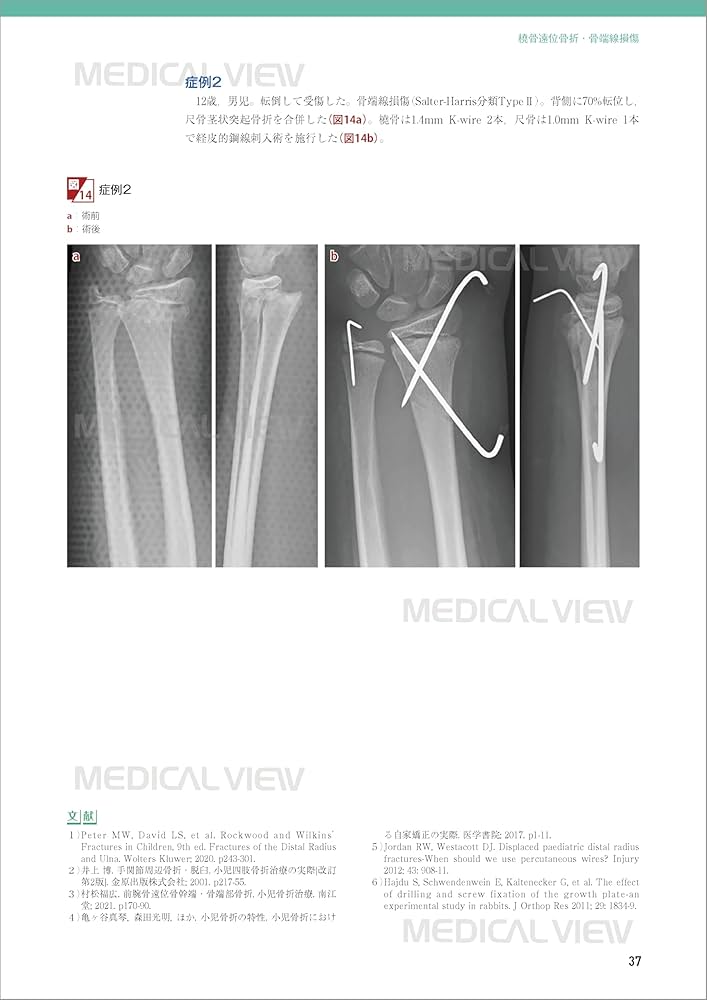

m3電子書籍 | 新OS NEXUS No.15 小児の骨折と手術[Web動画付]。小児の骨折と手術[Web動画付] (新OS NEXUS) | 大谷 卓也 |本。手・手関節の骨折・外傷の手術 (OS NEXUS(電子版付き) 3) | 岩崎。「小児の骨折と手術」大谷 卓也定価: ¥ 12000裁断済みです。書き込みマーカーありません。#整形外科#大谷卓也 #大谷_卓也 #本 #自然/医療・薬学・健康。ISBN978-4-7583-1392-6.jpg。健康・医学 HUMAN BIOLOGY Sixteenth Edition

• m3電子書籍 | 新OS NEXUS No.15 小児の骨折と手術[Web動画付]

• 小児の骨折と手術[Web動画付] (新OS NEXUS) | 大谷 卓也 |本